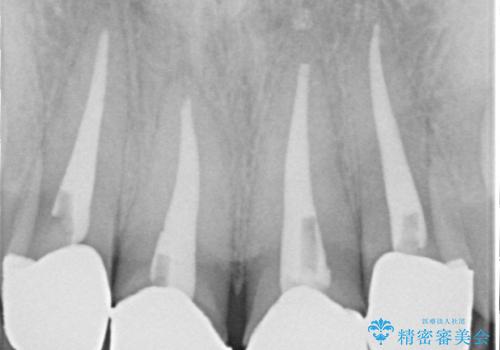

また被せものと土台の間に隙間があり、適合もよくない状態でした。

根管治療のやり直しは希望されなかったため、土台のやり替えと、より自然なオールセラミッククラウンへのやり替えを行いました。